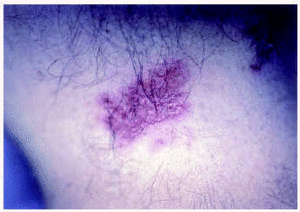

Se observaron placas eritematosas erosivas en las caras laterales del cuello, las axilas y las zonas inguinales (figs. 1 y 2).

Fig. 1.--Placas eritematosas erosionadas localizadas en las regiones axilares.

Fig. 2.--Placa eritematosa axilar con erosiones superficiales.